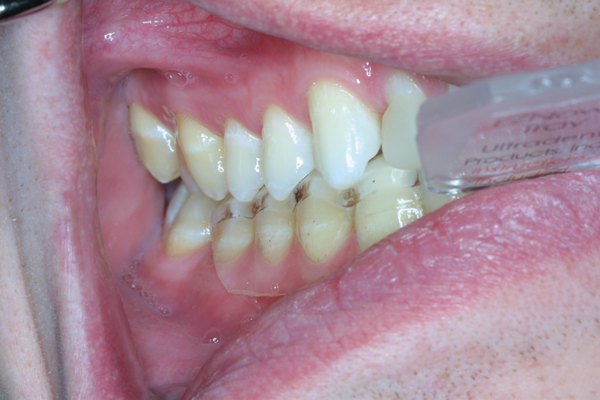

(14.) Smile photograph of the patient in Figure 13 immediately after removal of the arch wires and brackets, showing no white spot lesions or any yellow spots where the the bonded brackets were previously located.

Figure 14